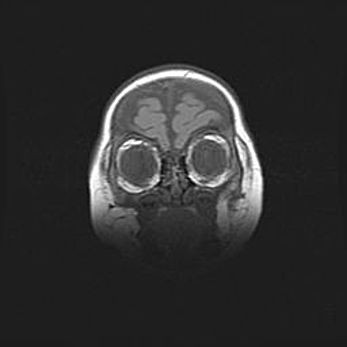

Аномалия Денди-Уокера. Признаки гипоплазии мозолистого тела.

Возраст: 5 месяцев 3 дня

Вес: 5550 г

Пол: мужской

Окружность головы: 39 см

Срок гестации: 40 недель

Аномалия Денди-Уокера – это порок развития головного мозга, для которого характерна триада симптомов: гипотрофия или аплазия червя мозжечка и/или полушарий мозжечка, расширение четвёртого желудочка с формированием ликворной кисты задней черепной ямки, гипертензионная гидроцефалия различной степени.

Гипоплазия мозолистого тела относится к дефектам внутриутробного этапа развития мозговой ткани, возникающим в процессе закладки структур головного мозга, что происходит на начальных этапах развития эмбриона.